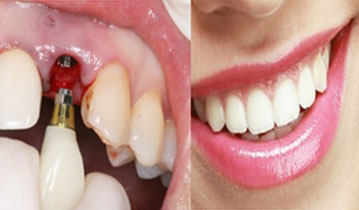

네비게이션 임플란트는 길을 알려주는 네비게이션처럼 치조골의 구조와 신경 위치를 파악하여 정확하게

임플란트를 식립할 수 있는 임플란트 방법을 말합니다. 네비게이션 임플란트는 3D CT를 통해 입체 영상으로 정확한 수술 계획을 세우고,

CT자료를 기반으로 구강에 끼우는 보조장치를 제작하여 잇몸 절개없이 작은 구멍을 뚫어 임플란트를 식립하여,

잇몸을 절개하는 수술방법보다 통증과 출혈이 적어 비교적 회복이 빠르게 나타납니다.